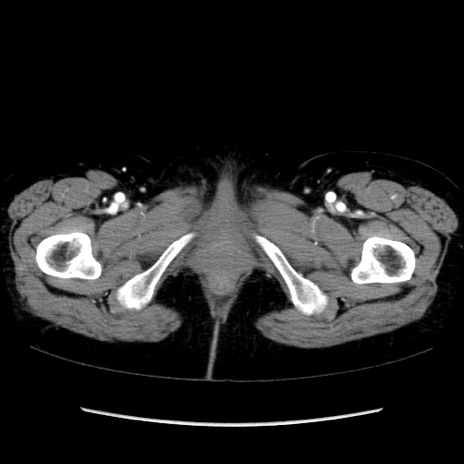

症例32(横断像)

【症例】40歳代 女性

【主訴】上腹部痛、嘔気・嘔吐

【現病歴】約9時間前頃から急に上腹部痛、嘔気、嘔吐が出現。改善しないため救急要請。

【既往歴】子宮頚癌(広汎子宮全摘術、放射線療法)、腸閉塞

【身体所見】腹部:平坦、軟、腸雑音亢進、上腹部を中心に腹部全体に圧痛あり。

【データ】WBC 8400、CRP 0.03